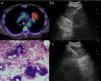

Other indications for EUS-B in malignancyIntrapulmonary tumors located adjacent to the mediastinal pleura are usually visible by endosonography. For that reason, EBUS as well as EUS are useful tools in diagnosing these pulmonary lesions in adults and children22–24 (Fig. 2). In a prospective trial, the feasibility of diagnosing intrapulmonary lesions by EUS-B-NA was demonstrated. In addition, the authors could confirm EGFR mutation and ALK fusion gene in some patients.25

Puncturing the left adrenal gland (LAG) with an EUS-gastroscope is a well-established technique to confirm intra-abdominal metastasis.19,30,31 This is also possible with the EUS-B scope to assess and puncture the LAG endoscopically (Fig. 3). In a prospective multicenter trial, adequate tissue sampling was feasible in 93% with the EUS-scope and in 89% with EUS-B-NA in patients with suspected metastasis of the LAG.32 However, despite these encouraging reports, currently the use of the EBUS bronchoscope for sampling the LAG is not generally recommended.19